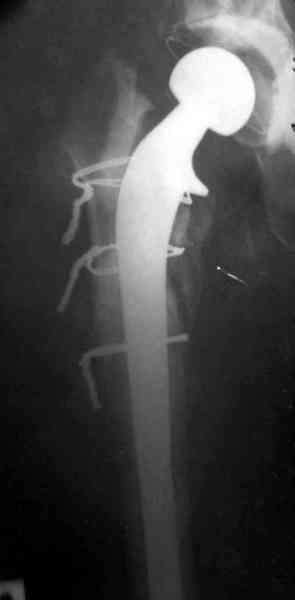

Приготовлен цемент из расчета: Tobramycin 2.4 g (2 флакона), Vancomycin 2 млн (4 флакона) и 2 упаковки цемента с добавлением дополнительного флакона цементной жидкости.

После обработки ацетабулярного компонента, ещё в мягком цементе в полости вертлужной впадины головкой бедренного компонента сделана выемка для головки, чтобы свежий цемент не прилипал к головке. Головку бедренного компонента завернул обычной стерильной фольгой, которую после образования выемки отлепил от головки.

Для спейсера в бедро использовал старый длинный бедренний компонент меньшего диаметра, облепленный со всех сторон цементом с антибиотиком.

№3-6 снимки с осложнением

и последние снимки.